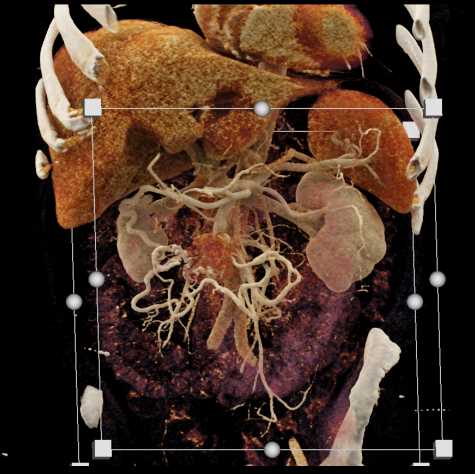

Carcinoid Tumor with Desmoplastic Reaction